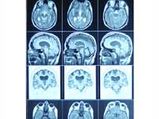

Learning To Read In Adulthood May Transform Brain

Cradle Of Maternity In The Brain Discovered